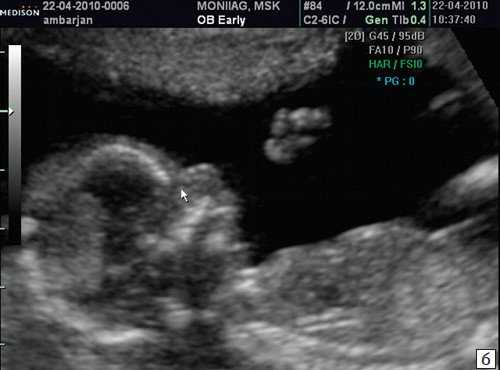

Считается, что носовая кость нормальна, когда она по своей структуре более эхогенна, чем надлежащая кожа и патологична, если она не видна (аплазия) (рис. 2) или ее длина меньше нормы (гипоплазия) (рис. 3). В случае одинаковой или меньшей эхогенности носовой кости чем кожи носовая кость считается патологической (рис. 4).

а) Носовая кость в 12 нед и 2 дня длиной 1,4 мм (меньше нижней границы нормы).

б) Носовая кость 2,1 мм в 14 нед у плода с синдромом Дауна.